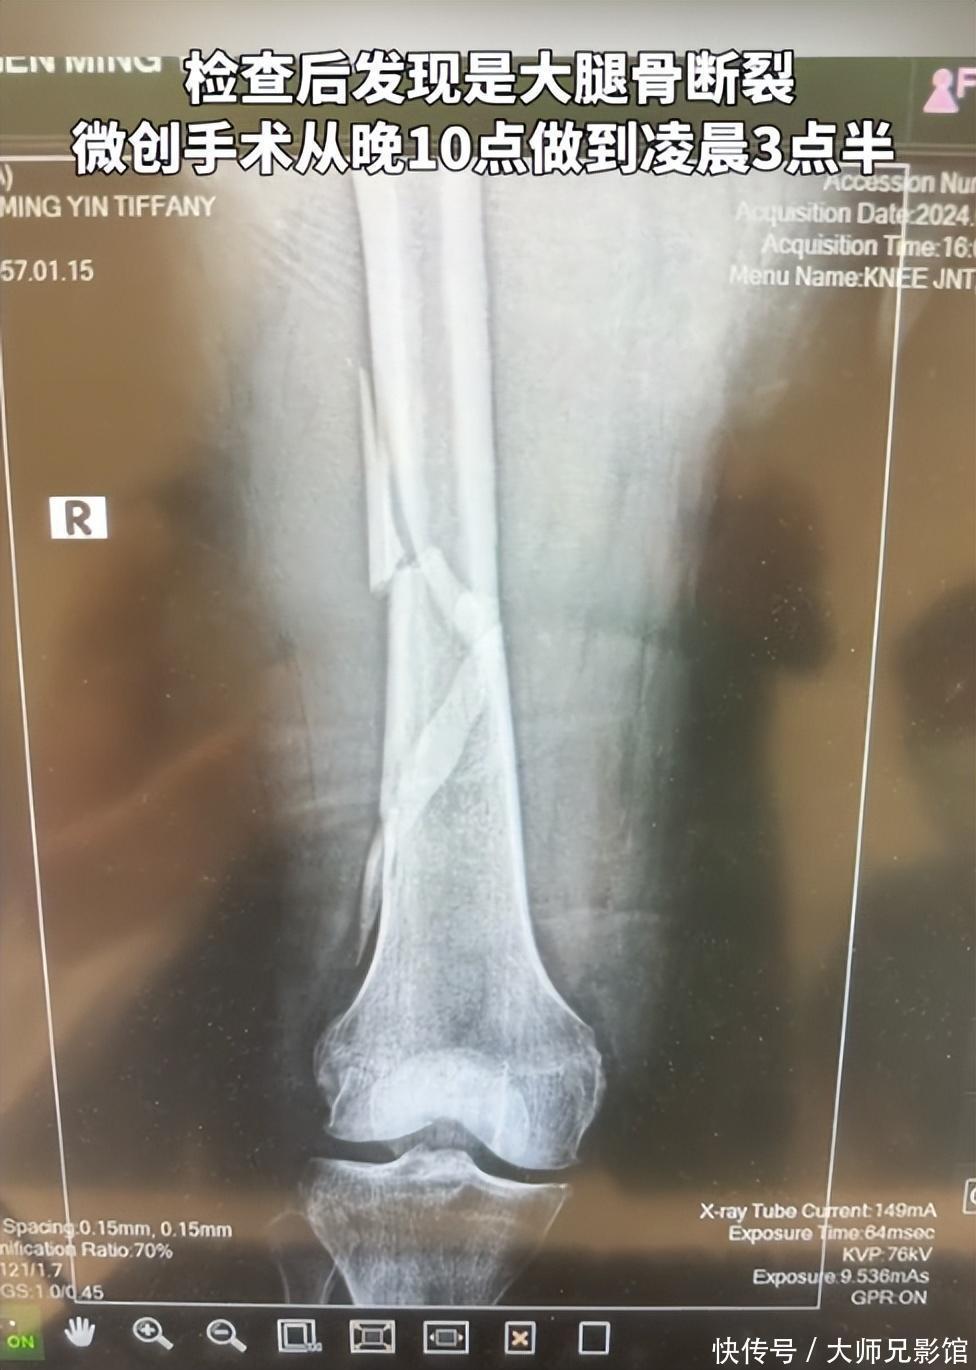

突发!向太豪宅中不慎滑倒,大腿骨裂手术5小时,向华强全程陪伴